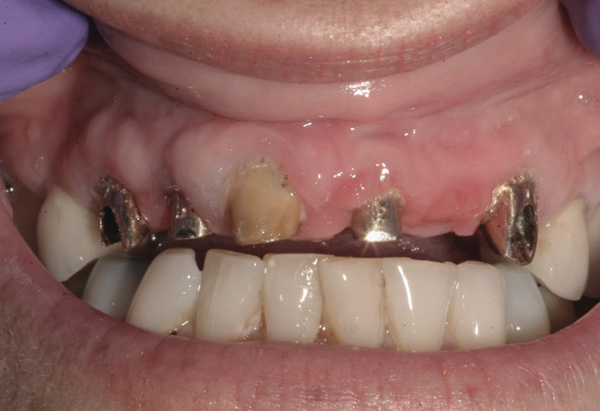

Background: This patient had a failing maxillary dentition and refused to wear a removable prosthesis. A staged approach was employed to retain some of his natural tooth abutments, and recession was noticed at the time of the impression for the second group of implants. Figure 1 shows the patient following insertion of the first set of implant custom abutments; the adjacent natural teeth are still present to support the provisional bridge. Seven months later, as shown in Figure 2, those first-stage custom abutments exhibited evidence of 1 mm to 3 mm of recession.

Results: A decision was made to re-prepare all of the abutments intraorally (Figure 3) so that all abutment margins would be at or below the gingival margin. (Of note, tooth Nos. 8 and 9, also shown in Figure 3, were later submerged for the case to be fully implant-supported.) While re-preparation greatly improved the esthetics of the final result, it required retraction cord placement, new impressions, and new castings.

Figure 2 After 7 months, the first-stage custom abutments exhibited evidence of 1 mm to 3 mm of recession.

Figure 2

Figure 3 Abutments re-prepared intraorally.

Figure 3